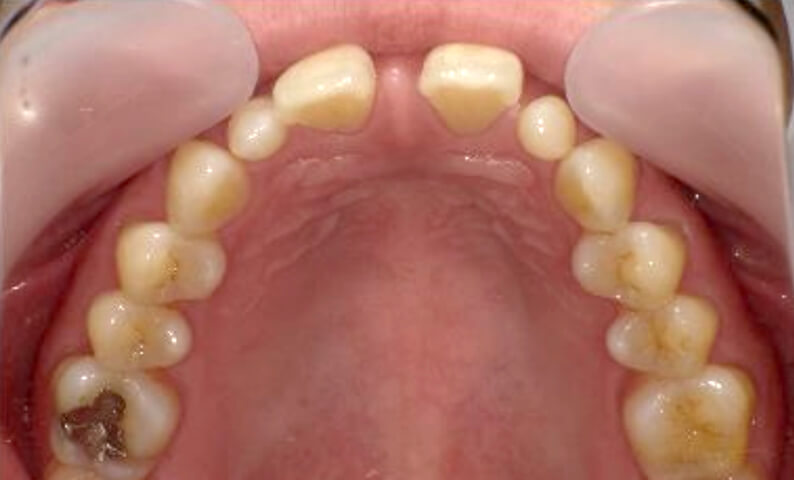

症例_003 上下顎の部分矯正

治療期間:12ヶ月金額:54万円+税男性八重歯前歯のガタガタ

| Before | After |

|---|---|

|